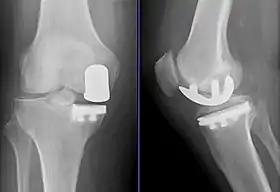

Radiographs of a knee arthroplasty of the medial compartment